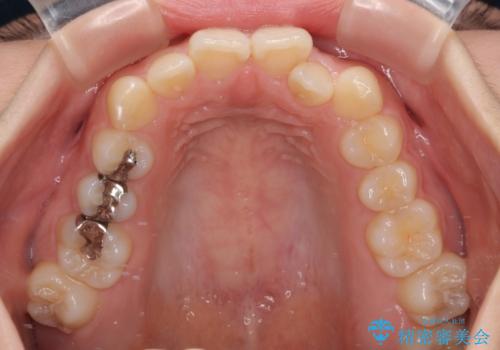

- 前歯のクロスバイトと口元の膨らんだ横顔の印象を気にして来院された患者様です。

レントゲン写真の分析結果からは、それほど口元が突出しているという結果にはなりませんでした。

しかしながら、唇を閉じたときに口元に緊張感があり、そのまま叢生を解消すると横顔が突出した印象になる可能性が高かったため、上下左右の小臼歯4本を抜歯して、ワイヤー装置にて矯正治療を行うこととしました。